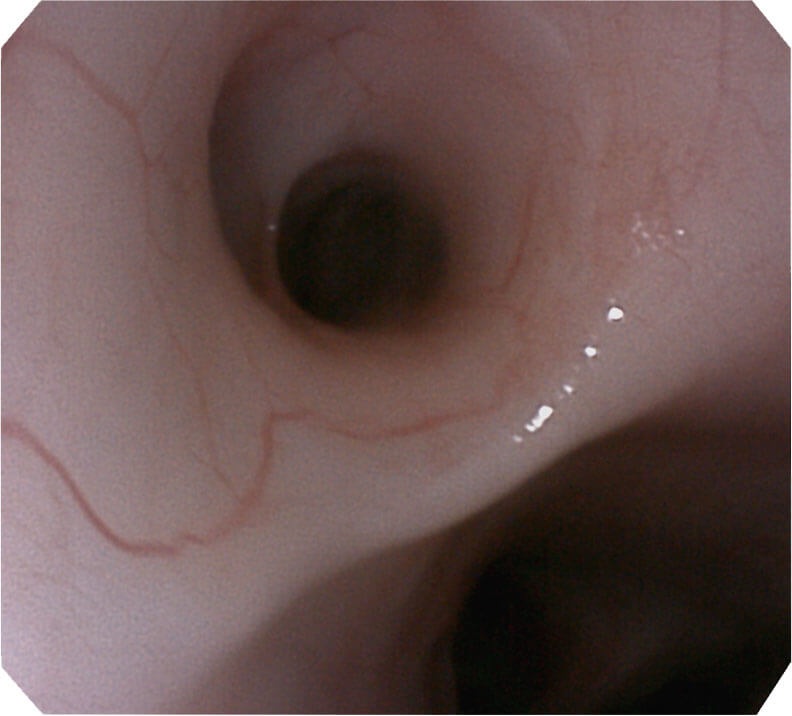

帮助医生更加清晰地观察气管表面病灶

120°视场角,满足更大视野范围的观察。配合 VIST 染色,助力呼吸系统疾病的诊断。

光电复合染色成像技术(VIST)是一种光学滤波和数字滤波相结合的染色成像技术,摒弃了滤光转轮而直接采用光谱组合的方案,加入了血红蛋白吸收高峰与次高峰的蓝紫光和绿光光谱,更有利于黏膜血管吸收,突显浅表层血管和中层血管的对比度,因而具备更高的图像对比度,有助于观察微细结构变化及病灶边界的观察。